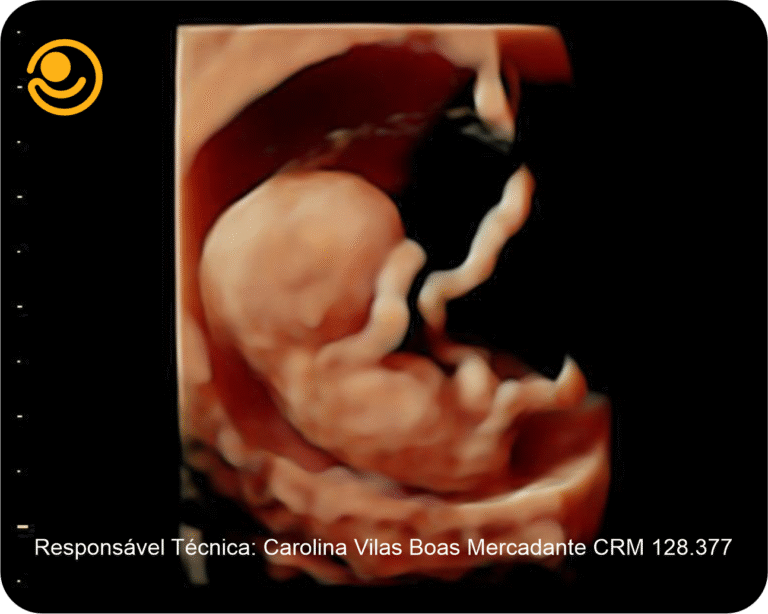

3D / 4D Live – Maior realismo nas imagens e mais precisão nos diagnósticos.

Imagens 3D / 4D

✓ Ultrassonografia 3D/ 4D com imagem em HD